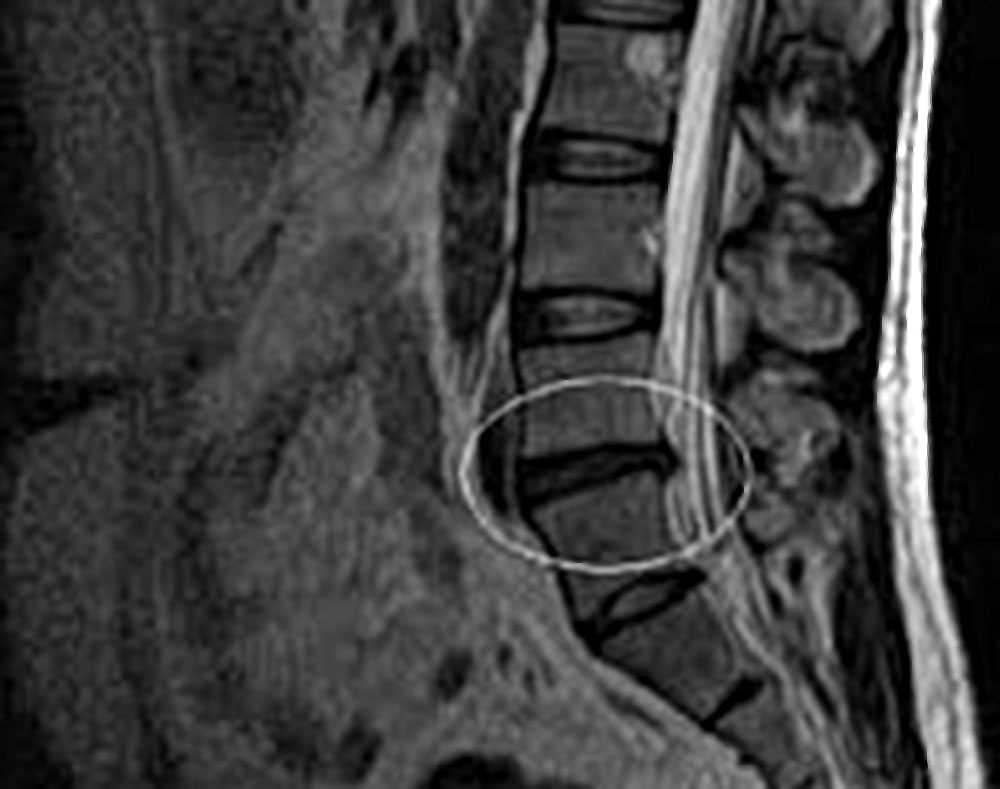

- визуальная диагностика: рентген, КТ или МРТ; наиболее четкий результат дает МРТ, которая хорошо визуализирует не только костные структуры, но и мягкие ткани различной плотности и позволяет четко увидеть нарушение формы диска;

Наиболее распространённой является диффузная грыжа диска L4-L5 наряду с диффузной грыжей диска L5-S1. Обусловлено это тем, что на поясничный отдел приходится наибольшая нагрузка.

Также для диагностики выпячивания проводится КТ или МРТ диагностика позвоночника. Эти исследования помогут не только визуализировать грыжу, но и определить состояние окружающих тканей, диагностировать сужение позвоночного канала, если оно имеется. При наличии показаний может быть назначена контрастная миелография. После обследования можно определить степень патологических изменений и назначить адекватное лечение. Если нервы не задеты, пациент жалуется только на боль, применяется консервативная терапия.